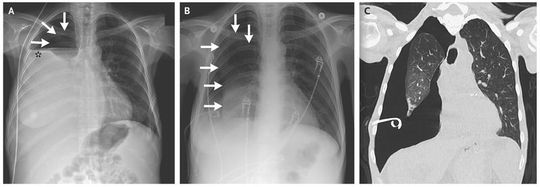

A 46-year-old woman with end-stage liver disease that was complicated by recurrent hepatic hydrothorax requiring multiple thoracenteses presented with breathlessness. Chest examination found no breath sounds on the right side. Radiography of the chest revealed a hydropneumothorax (Panel A; the arrows indicate pneumothorax, and the asterisk hydrothorax). The hydrothorax was drained with the use of a pigtail catheter, with persistent pneumothorax (Panel B, arrows). A computed tomographic scan of the chest showed trapped lung (pneumothorax ex vacuo) with thickened visceral pleura and no evidence of endobronchial obstruction (Panel C). Trapped lung is due to fibrous visceral pleural thickening from a chronic inflammatory process that prevents lung reexpansion. The noncompliant lung separates from the parietal pleura, and this space fills with fluid, with resultant hydropneumothorax. Drainage of the pleural fluid leads to pneumothorax ex vacuo because the lung cannot reexpand to fill the chest cavity. Once other causes of pneumothorax ex vacuo, such as endobronchial obstruction, are excluded, the management of trapped lung is surgical, with removal of the fibrosed visceral pleura to allow for the expansion of the underlying lung. In this patient, video-assisted thoracoscopic surgery with decortication and pleurodesis was performed, with complete reexpansion of the right lung.